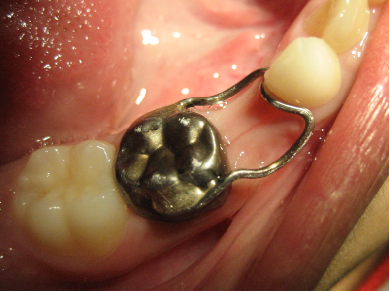

恒牙迟萌原因多种多样:

恒牙胚坏死、缺失或者错位。

多生牙、牙瘤或囊肿的阻碍。